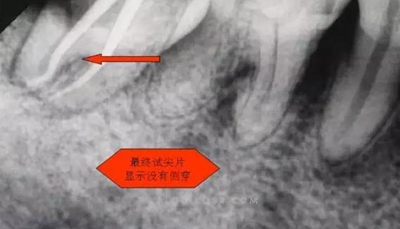

1.拍片基本可以確定遠(yuǎn)中頰側(cè)根管是一個(gè)融合根管,也就是常見的C型根管,粗大的根管口是扁形,根管同樣呈扇貝型,根尖孔粗大。而且在根管中上段較粗大,插針拍片后遠(yuǎn)中顯示根管有側(cè)穿的可能,但是通過內(nèi)窺鏡顯示是沒有任何側(cè)穿點(diǎn),也沒有滲血和患者有疼痛現(xiàn)象。這個(gè)病例告訴我們,有時(shí)候做根管治療,為了把根管做通和預(yù)備到位,必要的牙體組織去除是可以的,后期可以用冠修復(fù)來彌補(bǔ),如果不去除,本病例的根管治療,根充時(shí)可能會(huì)面臨充填不嚴(yán)密,從而導(dǎo)致根管治療的失敗,這是不可取的。

6.本病例,由于連接近遠(yuǎn)中2個(gè)根管的融合區(qū)頰舌徑過于狹窄,在x線片上顯示不清,而唯一能表現(xiàn)的是近遠(yuǎn)中分離的2個(gè)獨(dú)立的根管,將K銼放置到頰側(cè)根管內(nèi),有時(shí)在x線片上表現(xiàn)出根分叉處可能穿孔,這也是C型根管在x線上的重要特征。